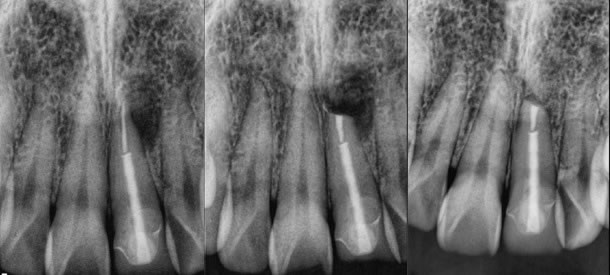

1. Thick or deeply set posts with well made coronal restorations. (figures 1-3)

Figures 1-3: pre-op / post-op / 9 months healing recall

Original root canal therapy performed by another endodontist and the crown was so perfect and the post deeply set. I performed the surgery on my friend with a great result.